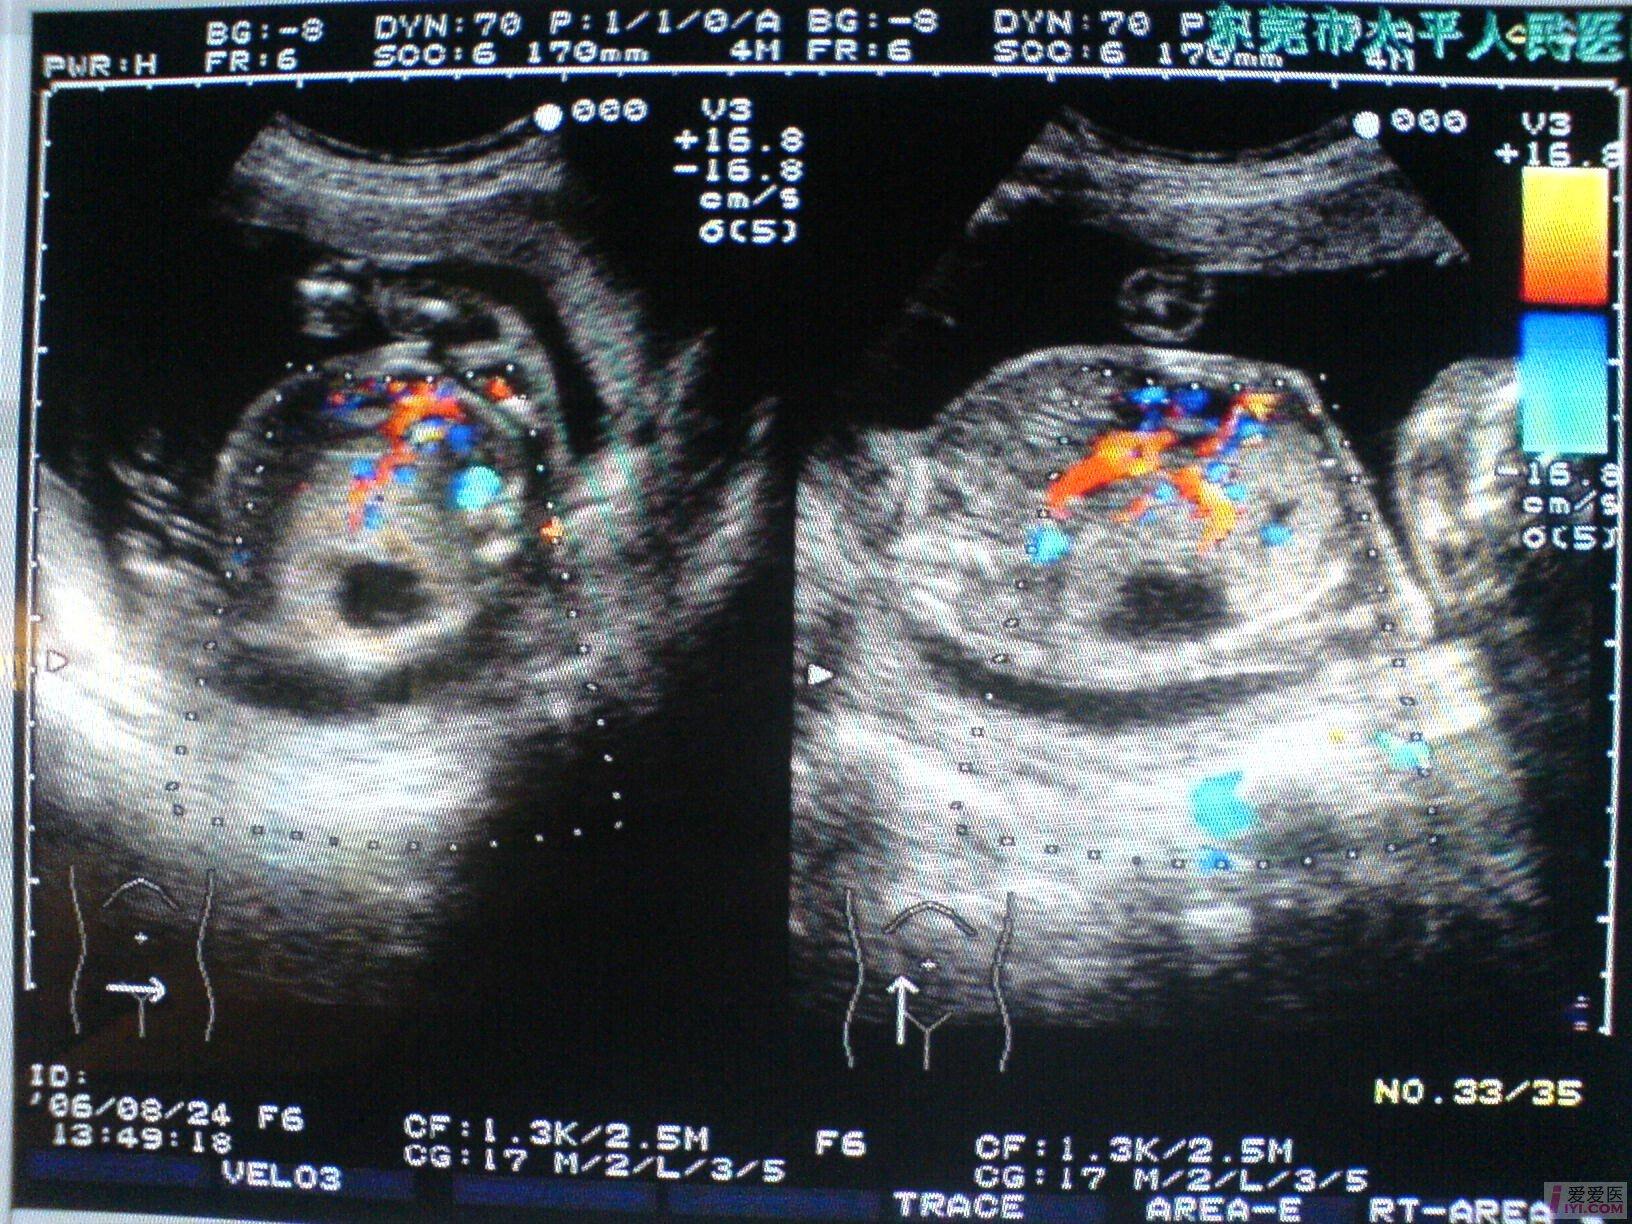

孕妇,女,33岁,G2P1,孕21周,常规产检。

B超所见:宫内单胎妊娠,胎头双顶径51mm,股骨长35mm,胎儿脊柱完整,肺实质回声增强,右侧肺叶内见31X18X17mm不规则无回声区,边界清晰,内透声好,CDFI:无回声区内未见血流信号。胎儿心胸比例失常,心脏明显受压,胎儿肝脏增大,位置下移,占据整个腹腔,回声增粗,欠均匀,未见胃泡回声,肝脏周围见宽4mm无回声暗区。胎动活跃,胎心搏动好,胎心律150bpm,胎盘附于前壁,厚21mm,回声均匀,最大羊水暗区深度74mm,透声好。

B超提示:1.宫内中孕,单胎存活,胎儿发育符合21周。

2.胎儿肺实质回声增强,右侧肺叶囊性占位,肝大,少量腹水。

请教:该例病例可否考虑胎儿肺囊腺瘤样变? [readperm]1[readperm]